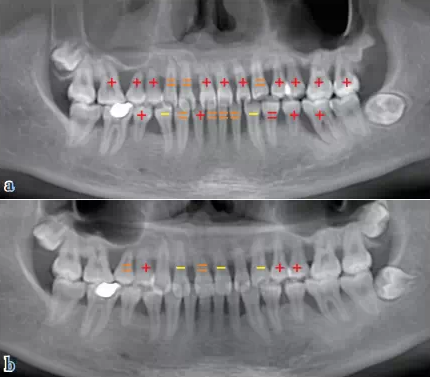

QQ圖片20150710154527.png

圖2 SRP、咬合干預(yù)后,電子探針檢查評估比較各項牙周臨床指標:牙周袋深度(花色:>6mm)等各項牙周指標明顯好轉(zhuǎn),(a)2011/12初診,(b)2014/05評估

QQ圖片20150710154752.png圖7 放射影像評估:與初診比較,牙槽骨骨量和骨密度明顯增加,上頜竇炎癥得到控制、明顯減輕;與初診比,牙齒松動顯著好轉(zhuǎn)(“+”表示松動Ⅲ度,“=”表示松動Ⅱ度,“-”表示松動I度),(a)初診,(b)兩年后評估